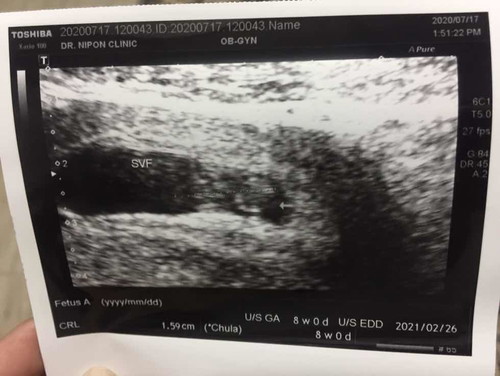

ถุงตั้งครรภ์

หมอบอกหัวใจเต้นดี ขนาดดี แต่ลืมถามหมอว่าถุงตั้งครรภ์ทำไมไม่กลมค่ะ ครั้งแรกที่ซาวด์กลม จะเป็นอะไรมั้ยคะ

ถุงยาวตามตัวน้องค่ะ 8วีค เริ่มยาวแล้วนะ